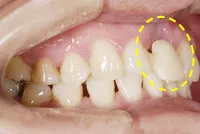

■治療前:奥歯が無いため噛み合わせが深く下の歯が全く見えない

噛み合わせが低いため全体的に歯が削れている

■治療後:下顎 左下5・6番、右下4・6番にインプラント治療

その他の歯に補綴治療をしたことにより、奥歯もしっかりと咬むことができ、奥歯ができたことにより噛み合わせも上がって下の歯も見えるようになり、審美的にも改善された

| 主訴 | 歯科治療をしても歯がすぐに欠けてしまう 奥歯が無いため、奥歯で咬めない |

|---|---|

| 治療方法 | インプラント治療 + 補綴治療 |

| 治療期間 | 約1年 |

| 通院回数等 | 約20回 |

| 費用 | 約250万円(税込) |

| リスク・副作用 | 術後の腫れ・痛み |